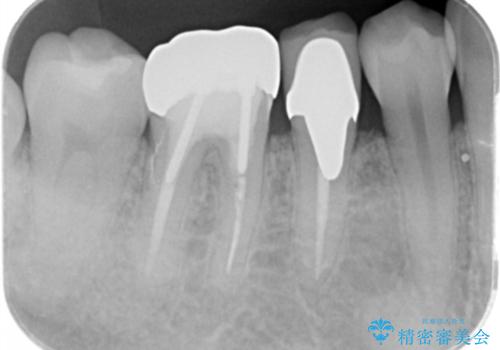

- 口を開けたときに下の歯の銀歯が目立つから白くしたいとのことで来院されました。

根管治療はご希望されなかったため、被せ物のみをやり替えていきます。

- 右下6 仮歯+ジルコニアクラウン 11,000円+121,000円費用は治療当時の料金となります